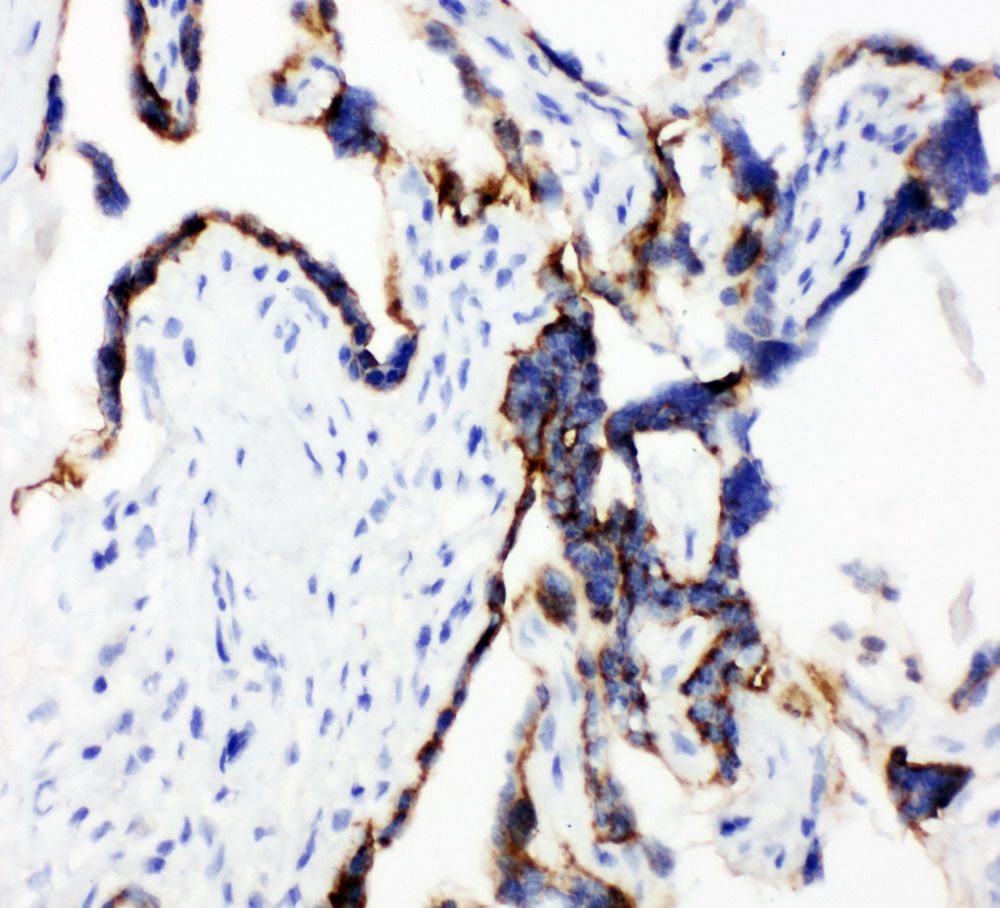

| Immunohistochemistry (IHC): | 1:50-400 |

| (Boiling the paraffin sections in 10mM citrate buffer,pH6.0,or PH8.0 EDTA repair liquid for 20 mins is required for the staining of formalin/paraffin sections.) Optimal working dilutions must be determined by end user. |